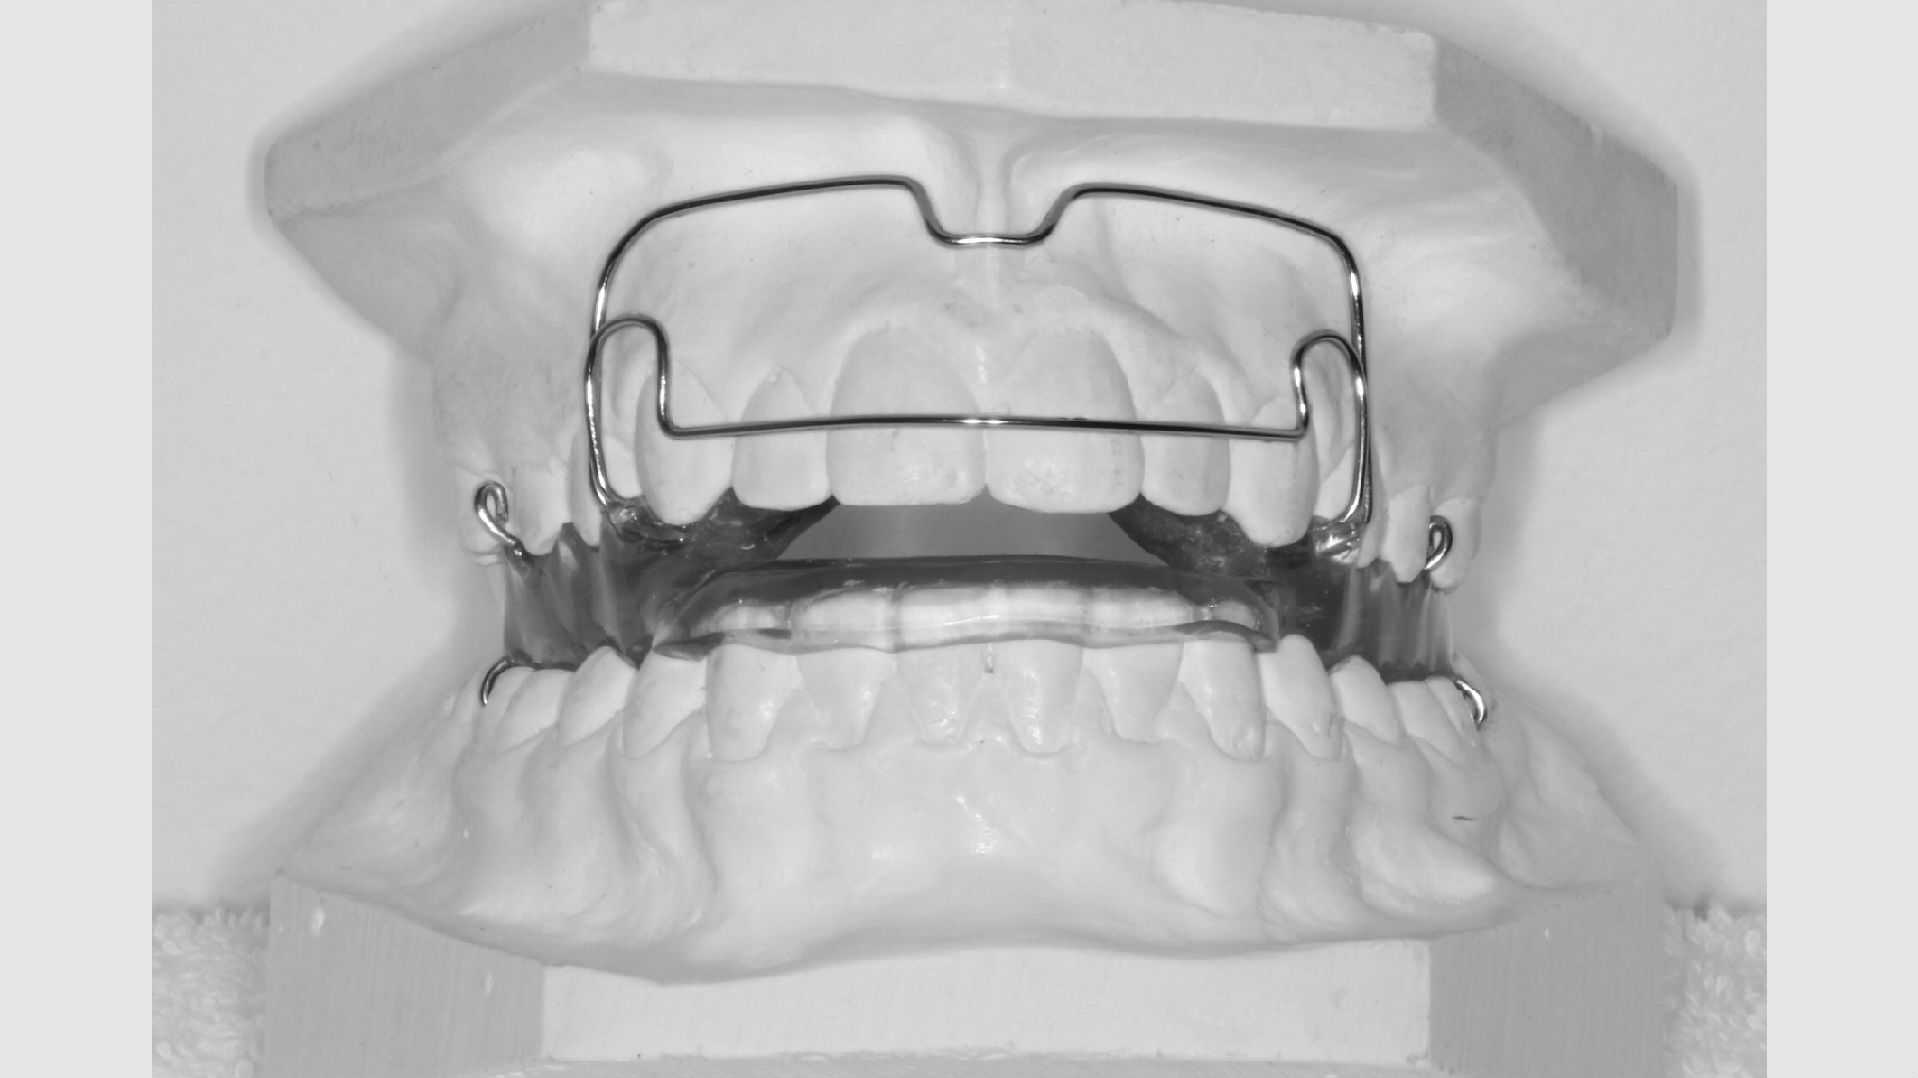

Aftagelige bøjler

Nogle tandstillingsfejl kan rettes med bøjler, du selv kan tage ind og ud. For at de skal virke, er det naturligvis afgørende, at du bruger bøjlen på den rigtige måde. Ofte vil det være nødvendigt, at du har bøjlen på i alle døgnets 24 timer - på nær når du spiser og børster tænder. Du vil altid få klar besked om, hvordan og hvor meget du skal bruge din bøjle.

Den aftagelige bøjle skal holdes godt ren. Det gør du med en tandbørste og lidt flydende, uparfumeret sæbe og ikke for varmt vand. Bøjlen kan ikke tåle kogende vand og kan ikke gå i opvaskemaskinen.

Når du får din bøjle, får du også en æske til at opbevare den i, når den ikke er i munden. Det er vigtigt at have æsken med sig og bruge den konsekvent, så bøjlen ikke forsvinder. Har I hund, er det vigtigt at sørge for, at hunden ikke kan få fat i bøjlen.